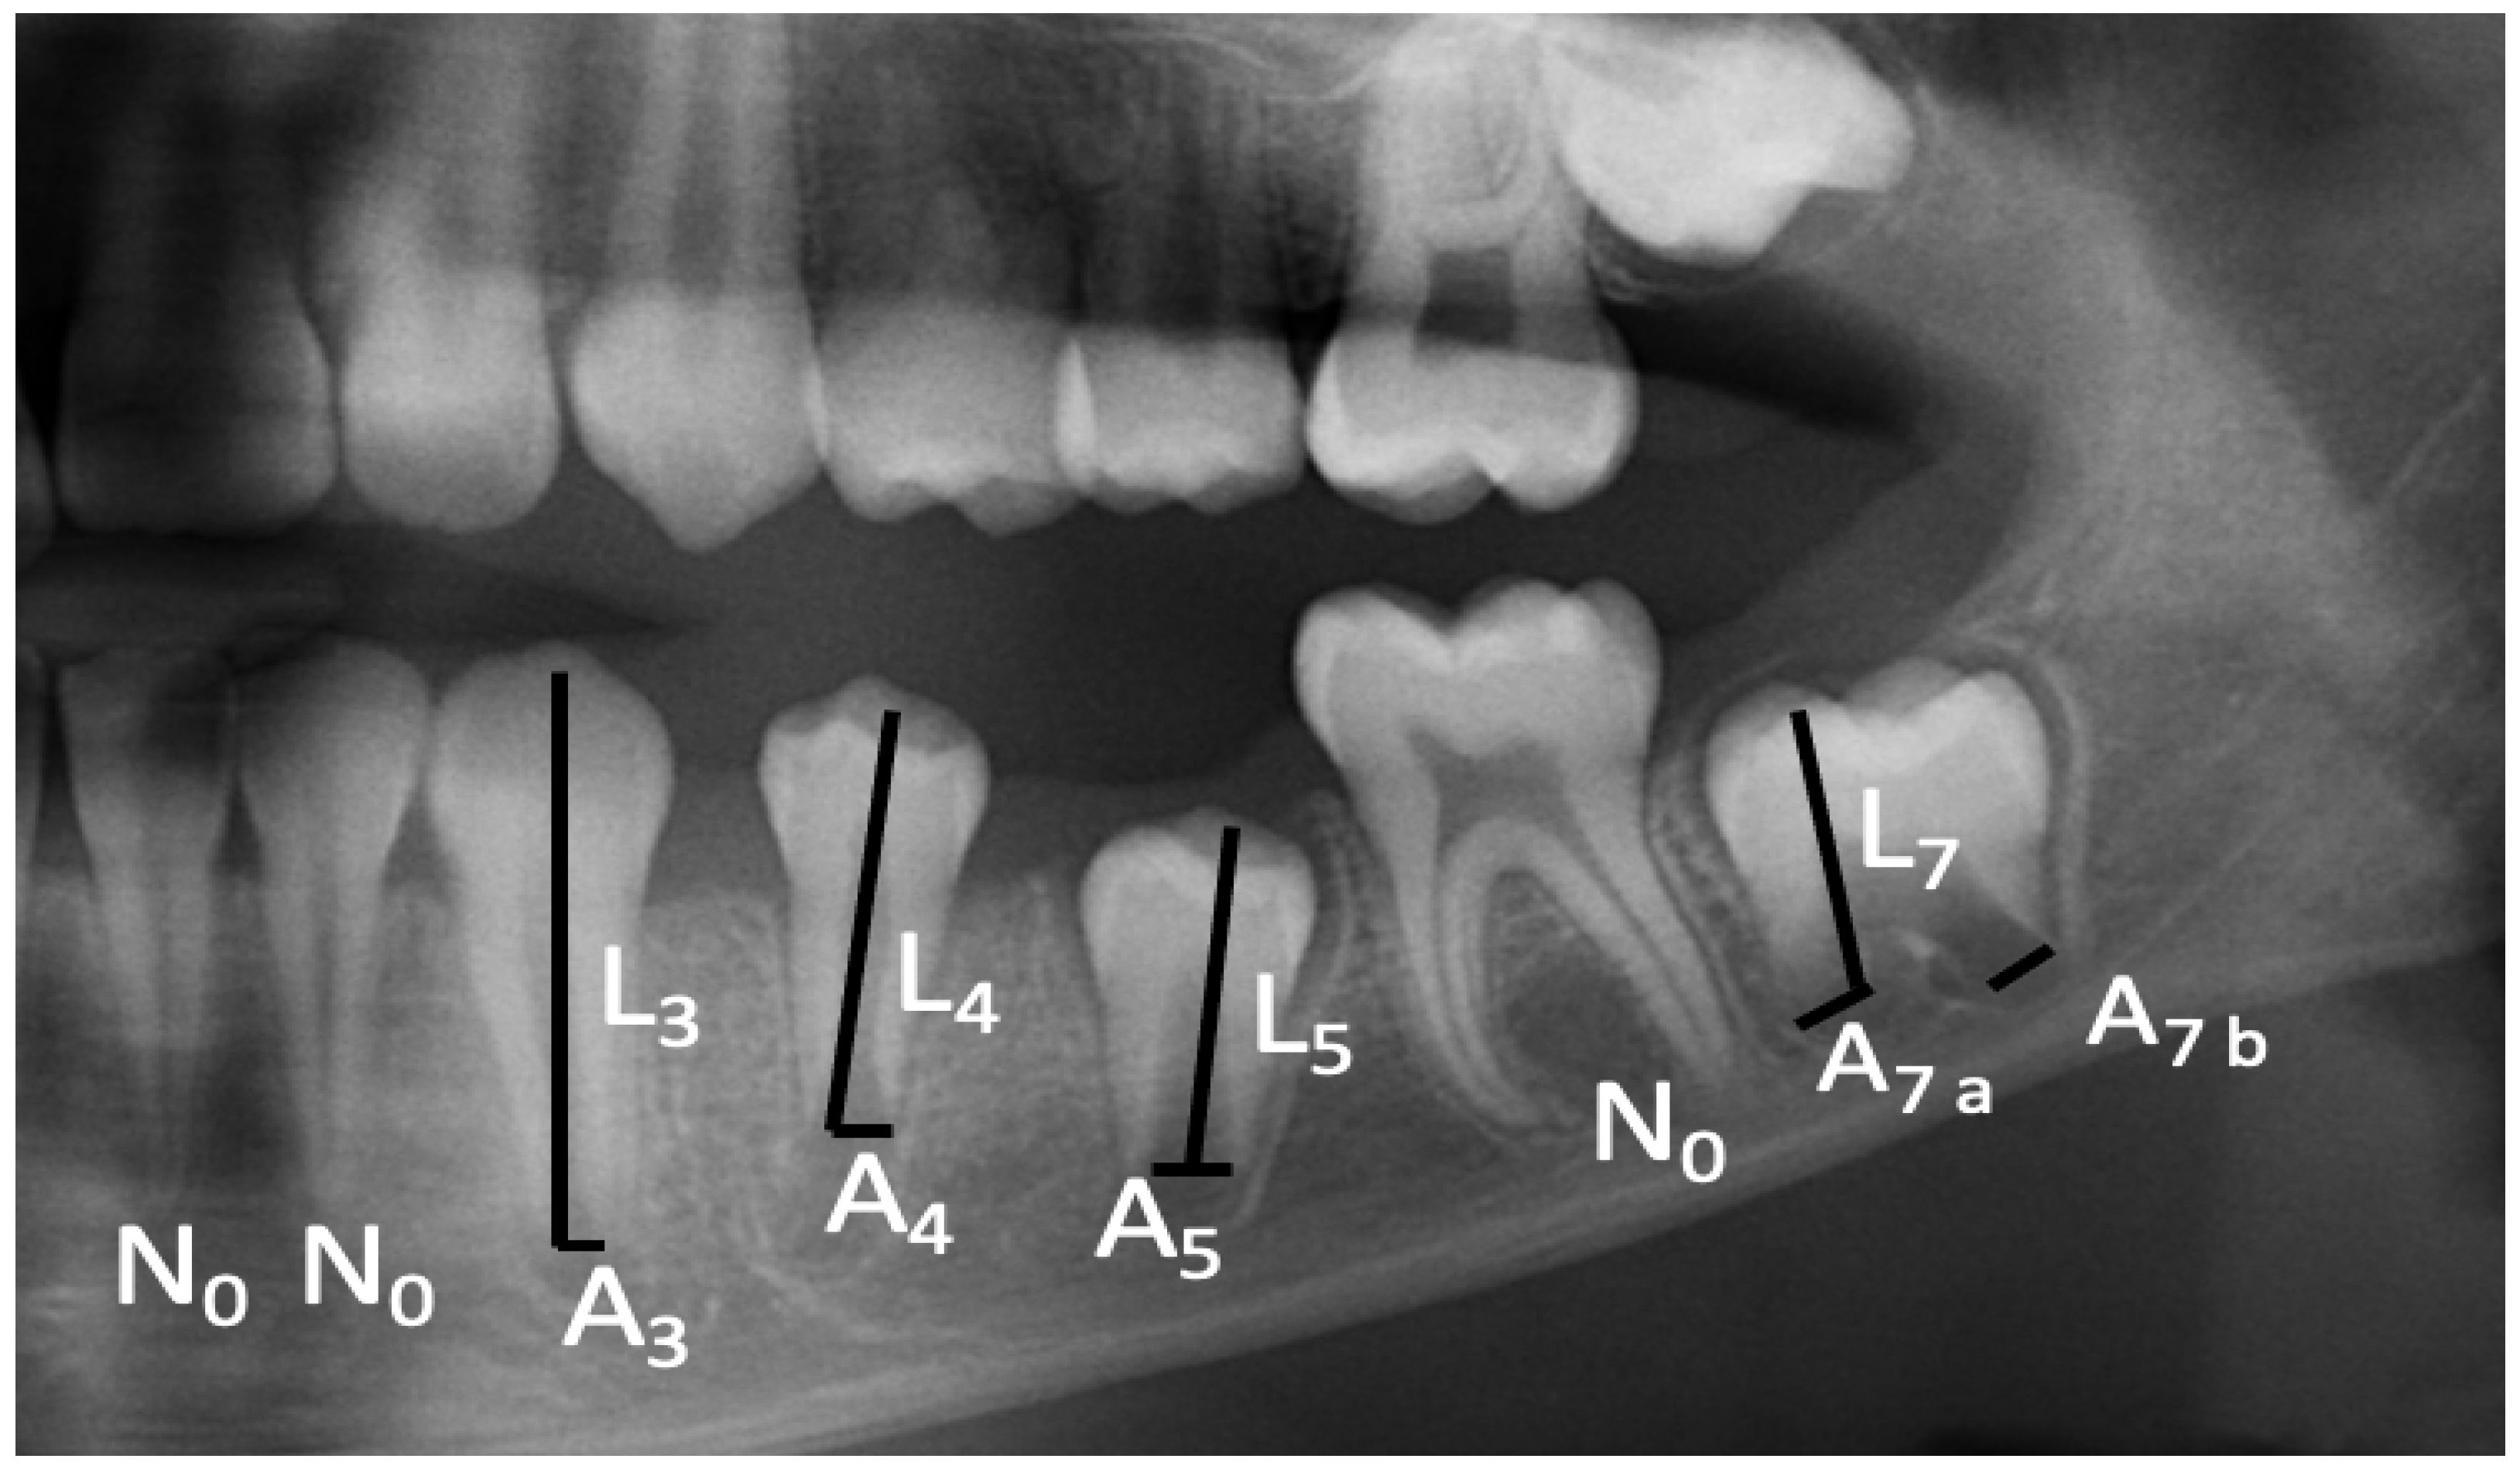

2.6. Dental Age Determination

2.7. Morphometric Measurements